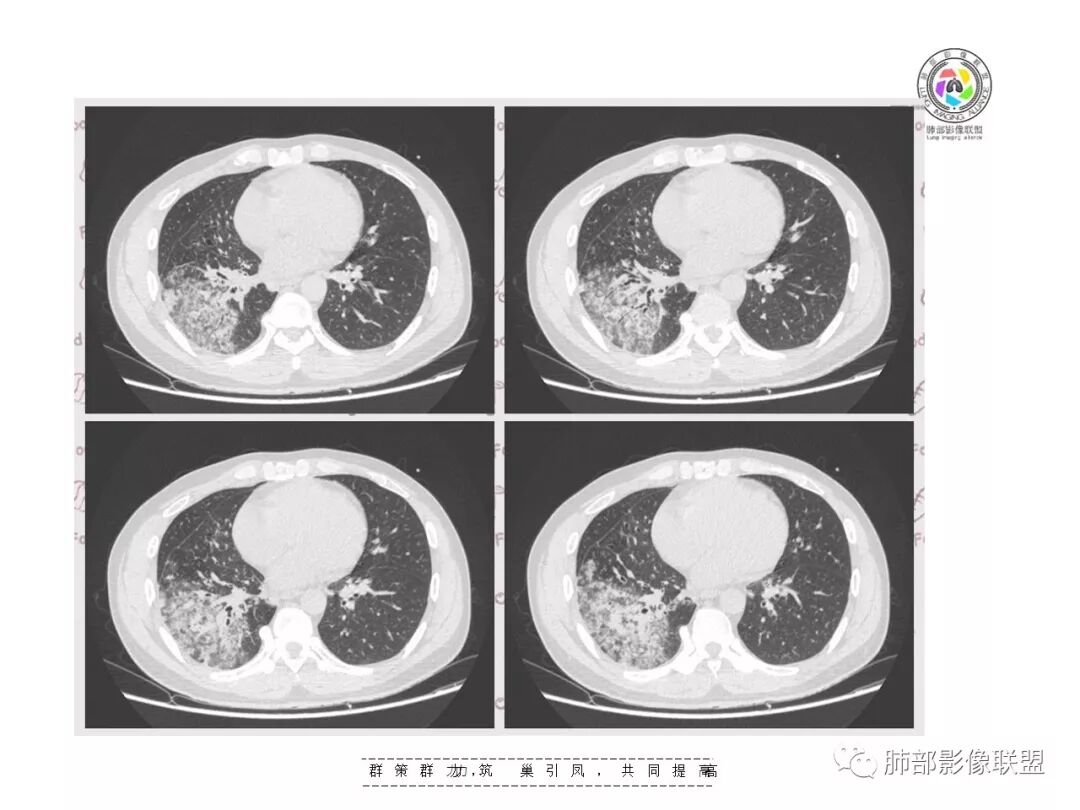

复查胸部CT视频显示肺部病灶明显吸收,淋巴结较前缩小。

患者在本院做了支气管镜,报告是有新生物,取了活检就转院了。病理结果是后来出来的。去肿瘤医院再做支气管镜,病理还是炎症。抗炎治疗(电话追问患者家属,具体不详)一个月后复查,右下肺病变基本吸收,肺门肿块明显变小;纵隔淋巴结基本都没了或者明显变小了

淋巴结肿大常见那么几种病变,转移瘤不符合,影像右下肺病变为炎性病变征象,前面已描述其特征:形态、走形、边缘(实质和GGO)、中央间质增厚、均匀强化、支气管充气征。都符合急性炎性病变。

支气管走形分布其实就两个问题。支气管远端部分堵塞,但大部分见支气管充气征明显。首先病变累及到支气管,支气管充气征远端病变常见两大类病变,气腔性的和引起气腔改变的,肺实质和支气管来源的均可以。

有树芽征,树芽征一般提示小气道受到影像,是炎性病变的特点。周围很多磨玻璃影,一般提示炎性病变,考虑急性为主,最起码有急性病变在其中。但该病人存在一个问题,其前基底段支气管有扩张,周围有实变,考虑原有病灶,有支气管扩张一般不考虑恶性肿瘤,肯定是慢性炎性病变。

病灶明显按叶、按段分布为主的,或者跟气道进来的病原菌引起气道壁的改变为主的,周围实变引起的,看CT冠状位、矢状位,如果能够沿着长轴重建更明显,就是沿着典型肺段分布的特点,如果急性沿肺段分布一般考虑气道来源。当然该患者说间质性可不可以?也可以,但是这样分布间质性也有特点。但我们周围外围分布为主,不按从肺门向外围肺叶段分布的话,那我们考虑外围的,它长轴会和胸膜平行的概念,常认为间质的。还有肺实质病变,理解是有差异的,肺隐球菌是肺实质病变?肺间质病变?应该两者都有。因为病灶在肺间质里面的,往往大片间质性病变,都是弥漫性间质病变,很少局限的。如果局限的,往往和中央间质相关的,就淋巴道局限有可能肺门淋巴结堵塞引起逆流受阻、分流受阻。或者沿着肺门淋巴结朝外围逆行性增生性增长。一般肺间质对称的,为疏松结缔组织,肺部疏松结缔组织弹性更好,纤维成分、纤维细胞多。第二巨噬细胞多。纤维化病变与免疫及相关的有关,也有特发的。间质相关性往往是弥漫的,主要其所有细胞,包括基质、细胞是相连相通的,特性是一致的,局限受累的比较少。